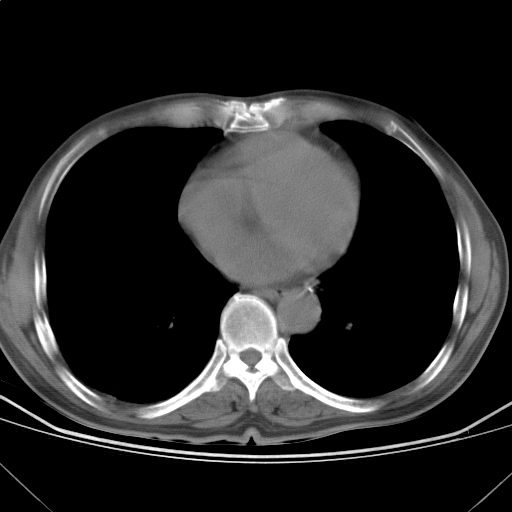

以下是引用随光逐影在2009-5-1 13:53:00的发言:[br]考虑为:1)两肺血行播散型肺结核;2)右肺下叶炎症感染。3)右侧胸膜增厚。